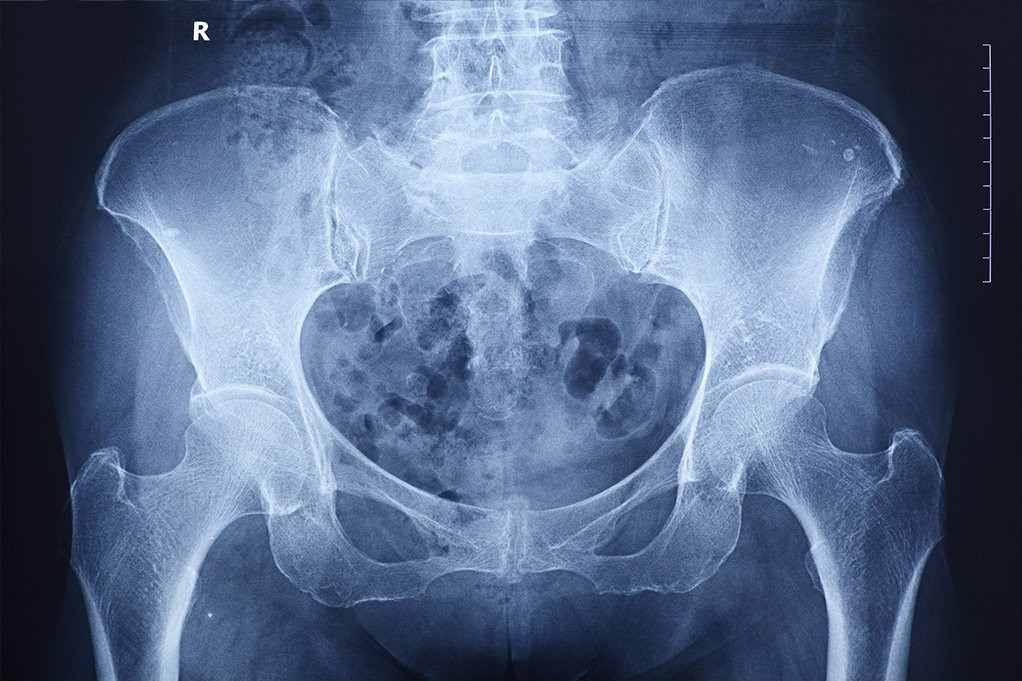

Lekari su bili šokirani kada su pronašli ogroman "vaginalni kamen" kako vreba unutar karlice žene. Kad su ženu pregledali, pronašli si masivni vaginalni kamen veličine pomorandže.

Bili su prisiljeni da urade trosatnu proceduru koja uključuje lasere kako bi razbili kamen i uklonili ga. Snimak sa rendgena pokazao je ogromnu veličinu koja je zauzimala veliki deo karlice.